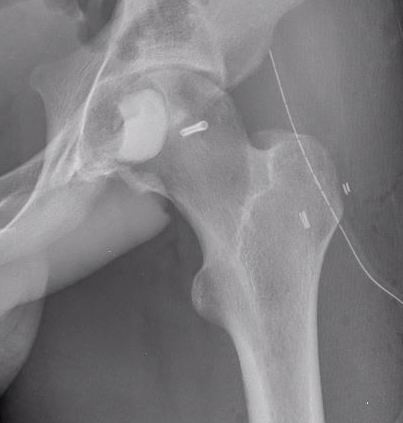

X-ray

Well defined eccentrically located epiphyseal lesion

- thin sclerotic reactive rim

- may have calcification

CT

Evaluate articular surface integrity / compromise

Identify chondroid matrix